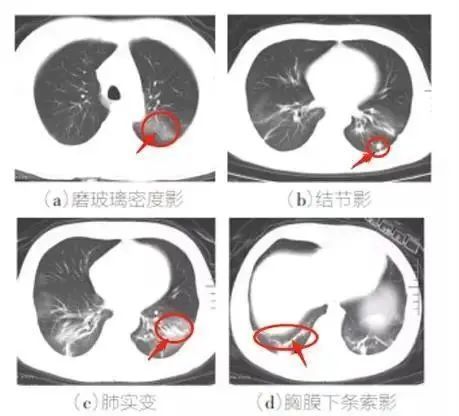

2、胸部CT特征:多發磨玻璃影、斑片影及實變影。

新冠病毒無癥狀感染者指呼吸道等標本新型冠狀病毒病原學檢測呈陽性,無相關臨床表現,如發熱、干咳、咽痛等可自我感知或可臨床識別的癥狀與體征,且 CT 影像學無新冠肺炎影像學特征者。